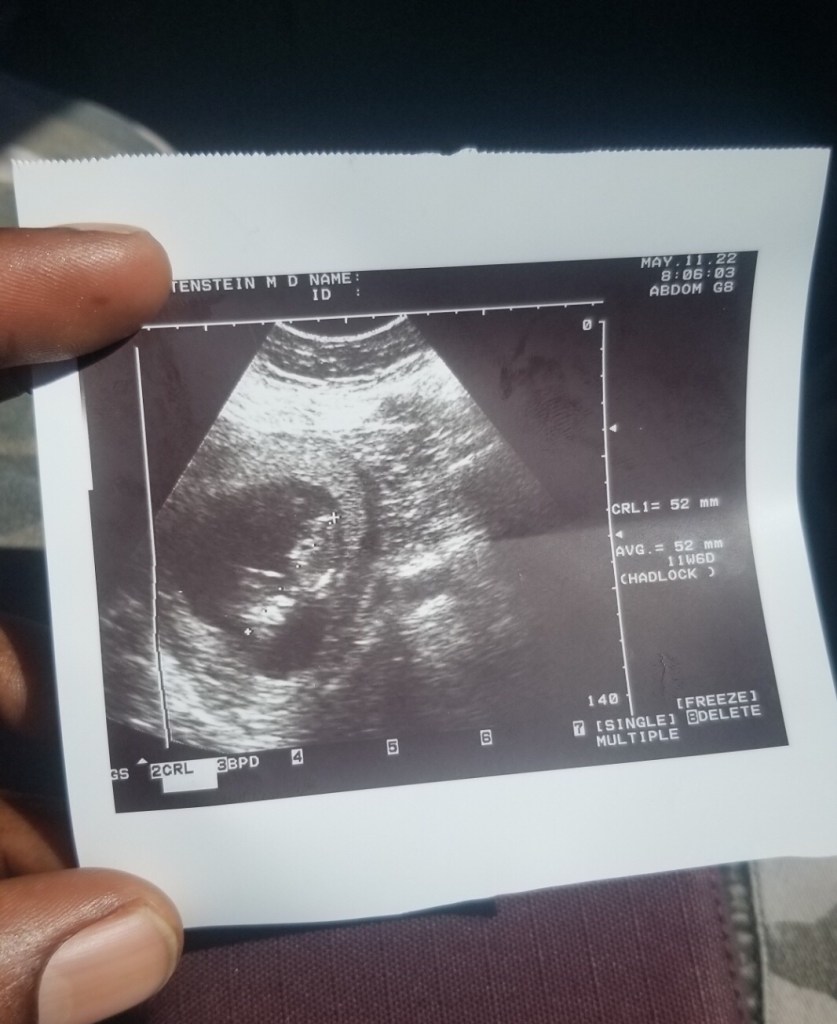

I had dreamed of becoming a mother all my life, but when it actually happened I was suddenly so grateful and yet so afraid of things going wrong.

This baby was already the new priority of my life, and it became pretty clear that I’d do anything for them to grow and be healthy.